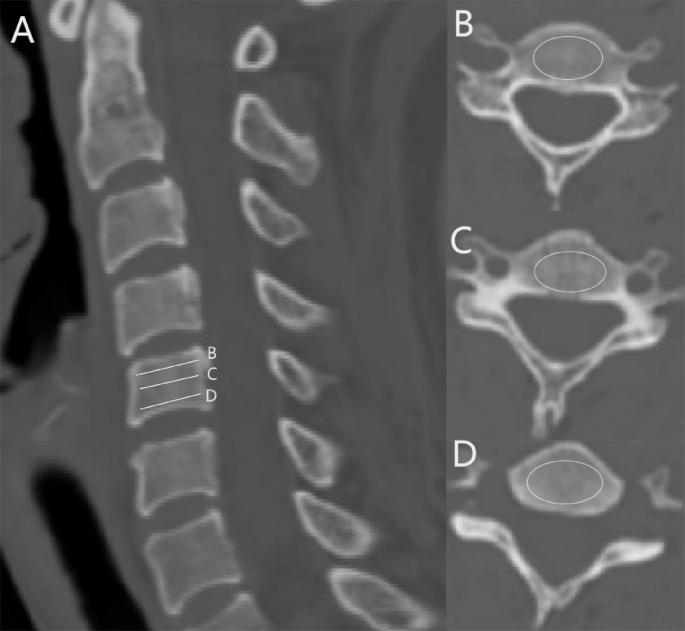

Method of HU measurement: CT imaging data were used to measure the HU value of the C5-C6 vertebral bodies according to a method previously described by our team9. The HU was determined by delineating an elliptical region of interest (ROI) that was centrally located within the cervical vertebrae, with the goal of including cancellous bone while excluding cortical bone margins, osteophyte formations, and bone sclerosis. The average HU value for each vertebral body was calculated based on the average HU values derived from three ROIs positioned horizontally across the cervical vertebrae (Fig. 1). All measurement data were independently evaluated twice by two spine physicians who were blinded to the clinical data. The average value between the two surgeons was taken as the final result.

HU value measurement (A) Cervical sagittal position (B–D) Cervical horizontal ROI (region of interest) HU value measurement.